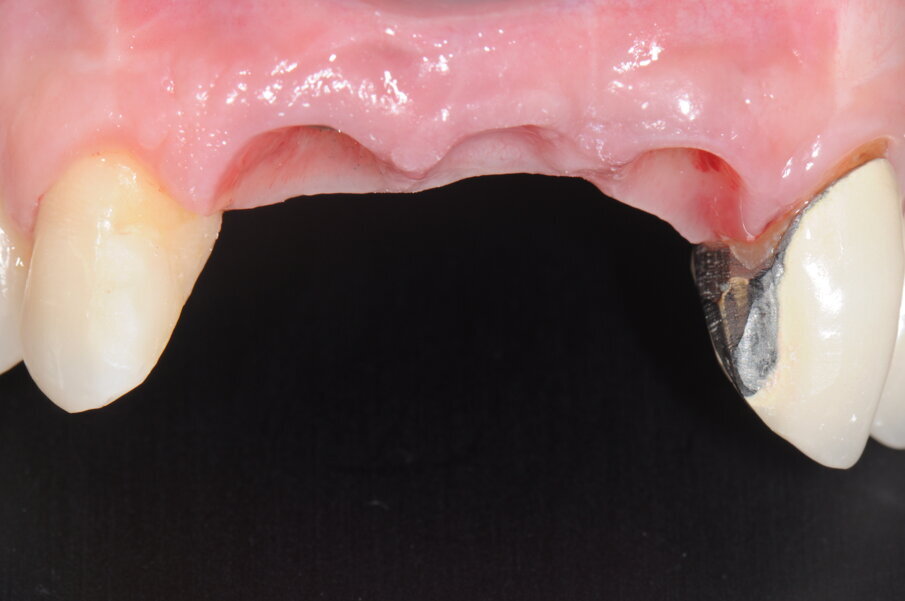

Fig. 5 - Situazione iniziale, visione occlusale..

Fig. 6 - Visione occlusale dopo avulsione elemento 1.1.

Fig. 7 - Visione frontale dopo avulsione elemento 1.1.